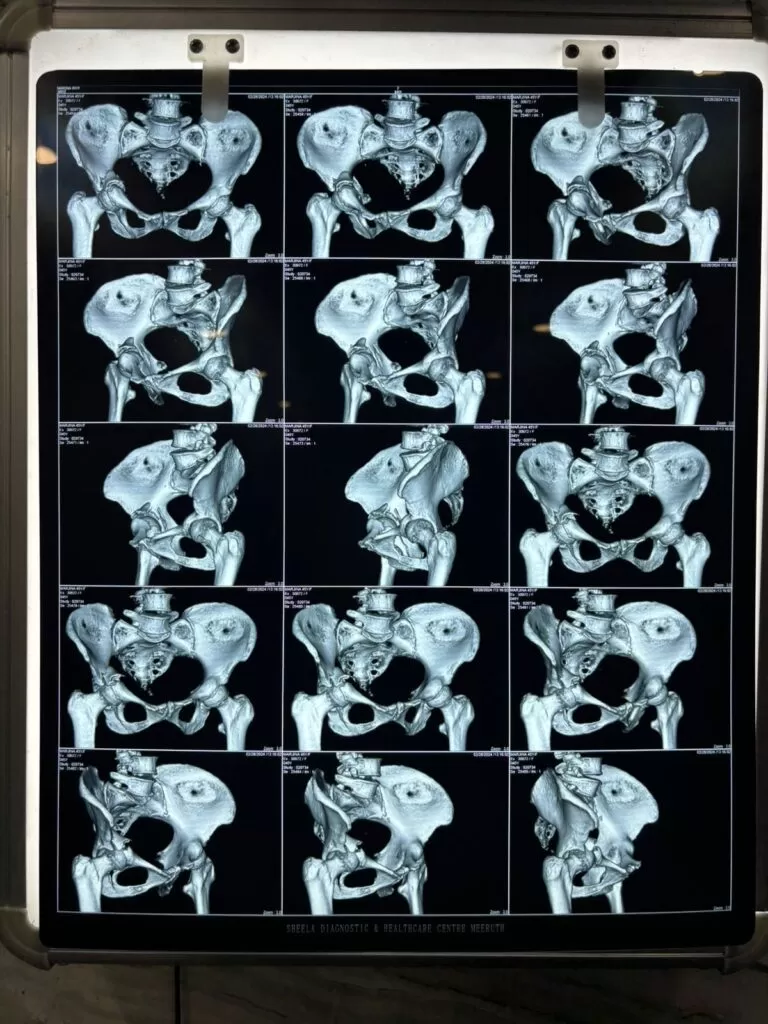

Mrs. Marzeena

Name: Mrs. Marzeena

Date of Operation: 03 Mar 2024

Age: 53 Years